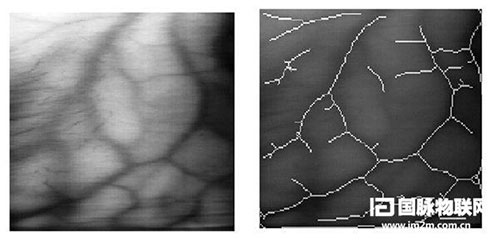

這款神奇的裝置名為 Smart Veins Locator(SVL),是一副可佩帶的頭盔式顯示器,可讓護士通過一幅浮現在病人皮膚上的“血管分布圖”實時查看到血管。

SVL 原型機將攝像頭和光源整合到頭盔式顯示器中,并在近紅外線的照射下捕獲病人的皮膚圖像。同時,通過某個組件實時地處理圖像、探測血管并將血管信息投射到一個透明的顯示屏上。護士通過眼鏡看到的血管實際上是覆蓋在病人皮膚上的分布圖。